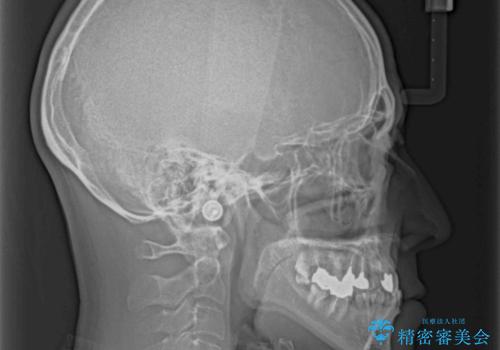

- 前歯のクロスバイトを気にして来院された患者様です。

骨格的に下顎が前方位ではありますが、歯並びが改善されれば正常咬合となることが分かったため、インビザラインを用いて咬み合わせを改善していくこととしました。